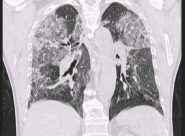

IL PROCESSO diagnostico del Coronavirus analizzato dal primario di Radiologia dell’ospedale Murri di Fermo, Gianluca Valeri, attraverso le immagini radiografiche e la tomografia computerizzata